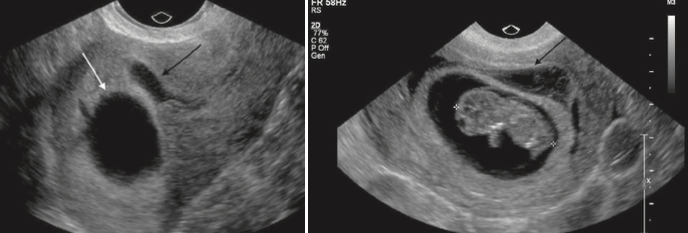

Diagnosis (2 different patients Embryo not in the field of view in A).

What is Subchorionic hemorrhage?

Results from elevation of the placental margin or marginal sinus rupture

May be associated with vaginal bleeding.

Hematoma <50% the size of gestational sac have no difference in pregnancy outcome than patients without. >50% shown to have increased rates of pregnancy loss.